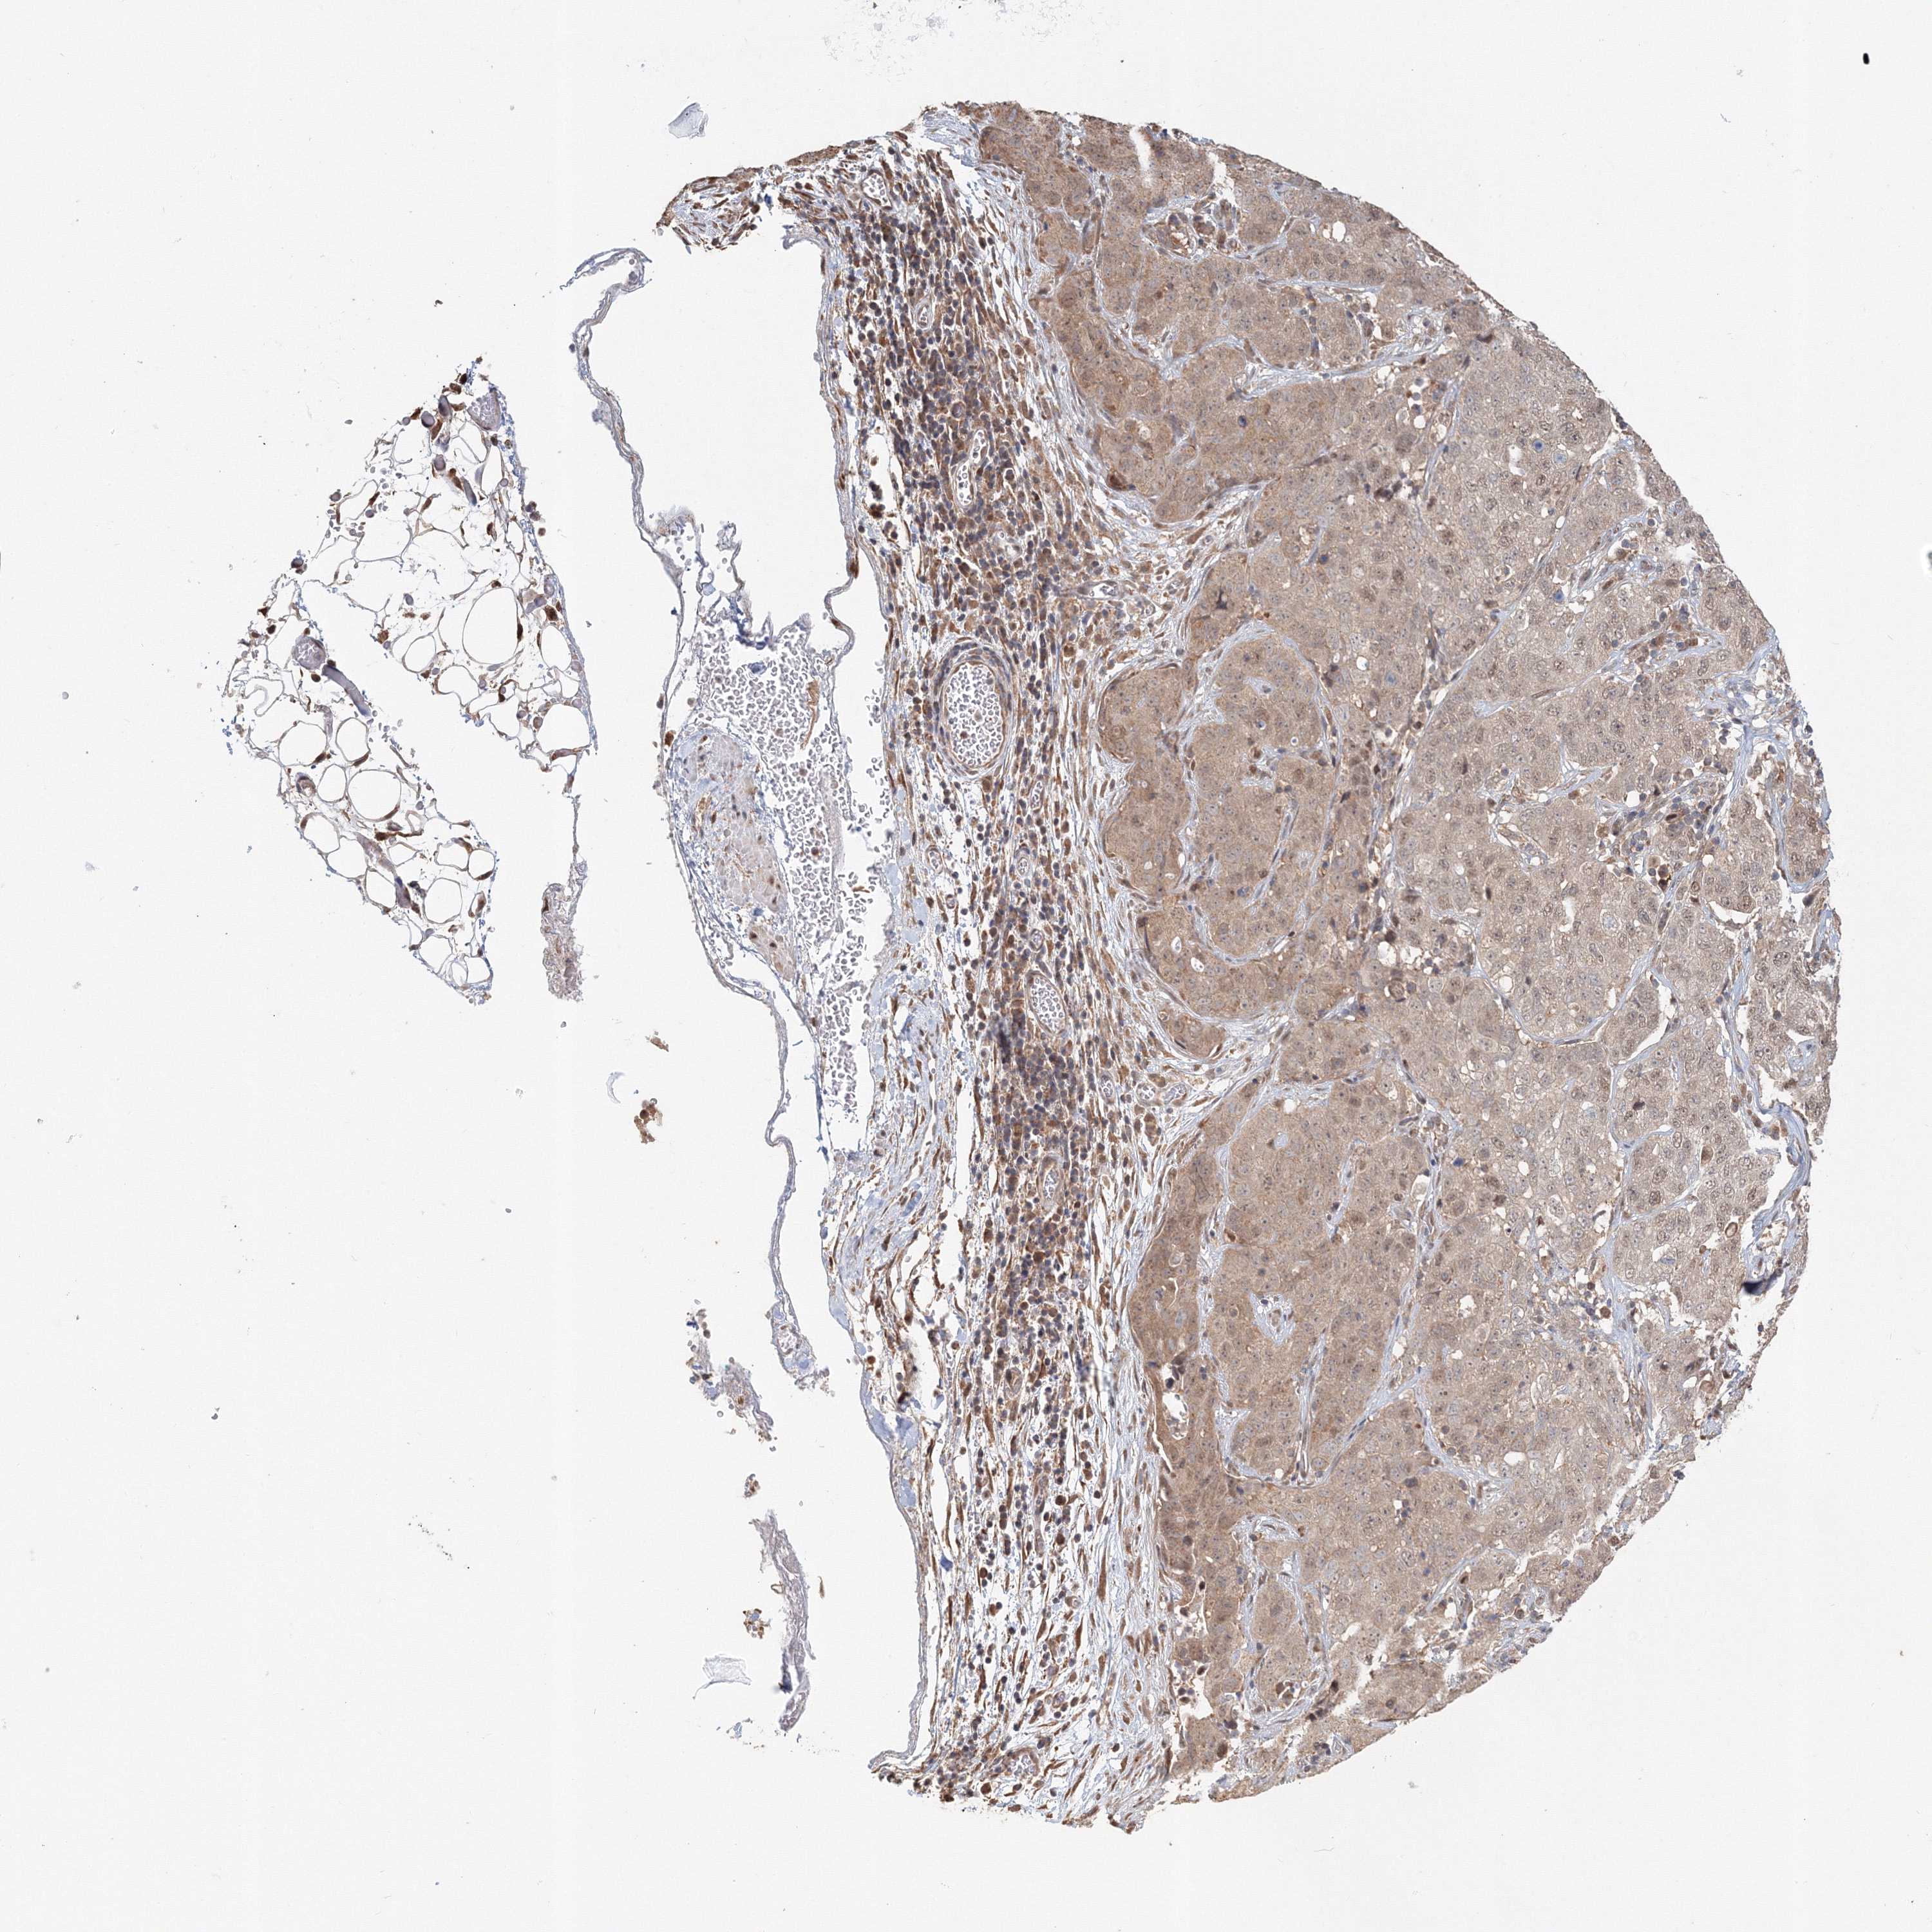

STOMACH CANCER - Protein expressioni

A mouse-over function shows sample information and annotation data. Click on an image to view it in a full screen mode. Samples can be filtered based on level of antibody staining by selecting one or several of the following categories: high, medium, low and not detected. The assay and annotation is described here.

Note that samples used for immunohistochemistry by the Human Protein Atlas do not correspond to samples in the TCGA dataset.

Antibody stainingi

Antibody staining in the annotated cell types in the current human tissue is reported as not detected, low, medium, or high, based on conventional immunohistochemistry profiling in selected tissues. This score is based on the combination of the staining intensity and fraction of stained cells.

Each image is clickable and will lead to virtual microscopy that enables deeper exploration of all samples and also displays staining intensity scores, fraction scores and subcellular localization as well as patient and tissue information for each sample.

Antibody HPA036921

Antibody HPA036922

Staining

High

Medium

Low

Not detected

Intensity

Strong

Moderate

Weak

Negative

Quantity

>75%

75%-25%

<25%

None

Location

Nuclear

Cytoplasmic/membranous

Cytoplasmic/membranous,nuclear

Adenocarcinoma, NOS